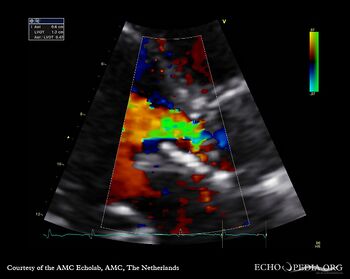

Aortic valve endocarditis with vegetation

Case description: This patient had endocarditis with an aortic valve vegetation

PLAX showing an aortic valve vegetation PLAX Excentric aortic valve regurgitation